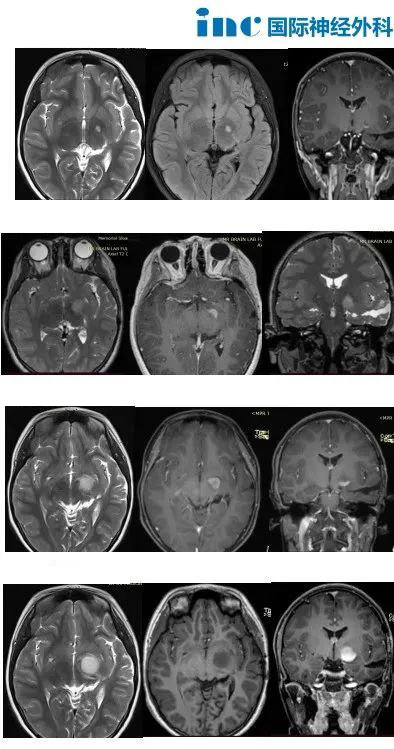

11岁女孩Judy-左侧丘脑和颞叶内侧胶质瘤术后复发

11岁女孩Judy,由于整整1年的发育迟缓,2020年,父母带着Judy去看儿科医生,对于身高停止增长的问题,儿科医生建议她做脑部CT,问题果然出在脑袋上。医生在Judy脑袋的左侧鞍旁发现了占位性病变。

手术治疗后病理结果显示:毛细胞型星形细胞瘤,WHO I级。

术后Judy定期接受核磁共振对比检查。

然而,2022年,复查MRI发现左侧丘脑微小异常信号,手术的医生建议服用靶向药物或化疗,但当时没有采取任何治疗措施,只是继续通过复查核磁共振进行观察。

2023年,再次复查MRI显示病灶明显增大,于是他们再次咨询了之前的手术医生。医生还是建议服用靶向药物。

但,靶向治疗3个月后复查MRI显示病灶进一步增大和强化。

术中核磁共振监测下的激光消融全程热成像图